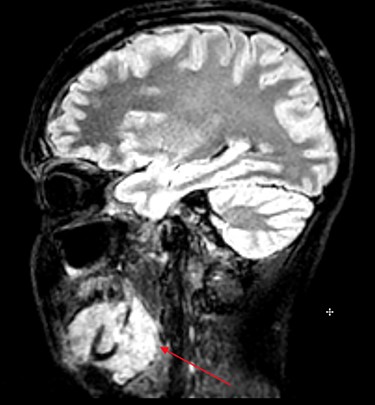

MRI head (sagittal view) showing Burkitt’s infiltrating the mandible and oral mucosa.